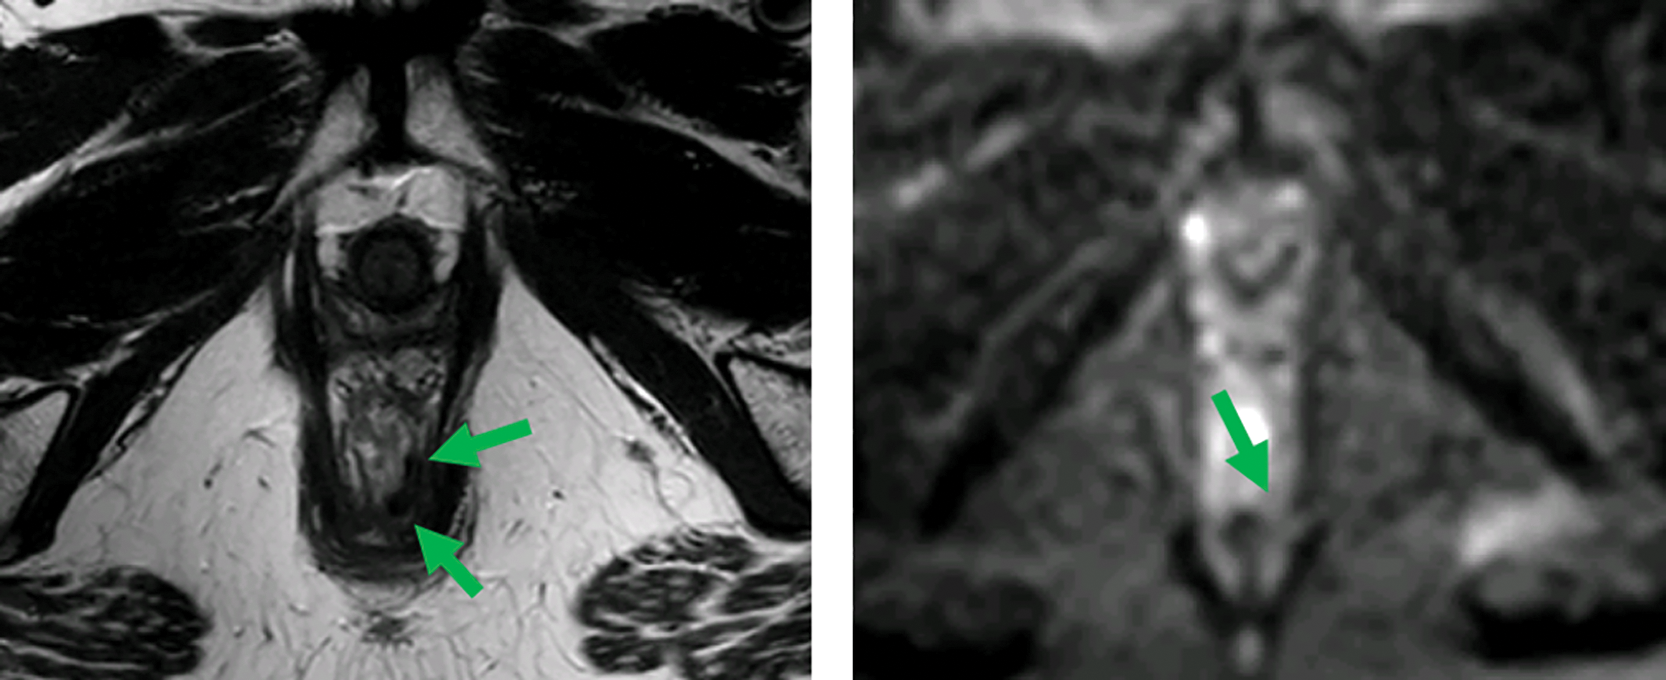

Primary tumor response: Differentiate fibrosis/scar from residual tumor. Features of a complete response include a dark T2 scar without intermediate signal mass and the absence of restricted diffusion (Figure 1).

Figure 1

MRI before (top) and after (bottom) neoadjuvant therapy. Axial T2‑weighted and b1000 DWI images show a distal rectal tumor (red arrows). After neoadjuvant therapy, a T2 dark, fibrotic remnant is seen without restricted diffusion (green arrows), indicative of a clinical complete response.